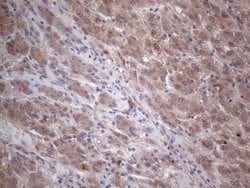

MTF1 Monoclonal Antibody for Western Blot, IHC (P)

| Immunohistochemistry (Paraffin), Western Blot | |